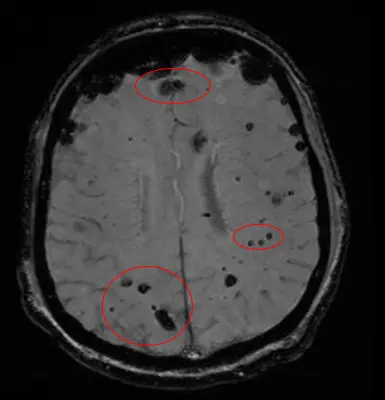

Cavernomas are enlarged and deformed blood vessels gathered into clusters. These clusters, called angiomas, may look bubbly, like raspberries. A cavernoma can appear in the brain, spinal cord or other parts of the nervous system and body, including on the skin and eye.

Cerebral cavernous malformations, or CCMs, are abnormal blood vessels that gather into clusters about the size of a raspberry.

Cavernomas are diagnosed using magnetic resonance imaging (MRI). Treatment for cavernomas includes: